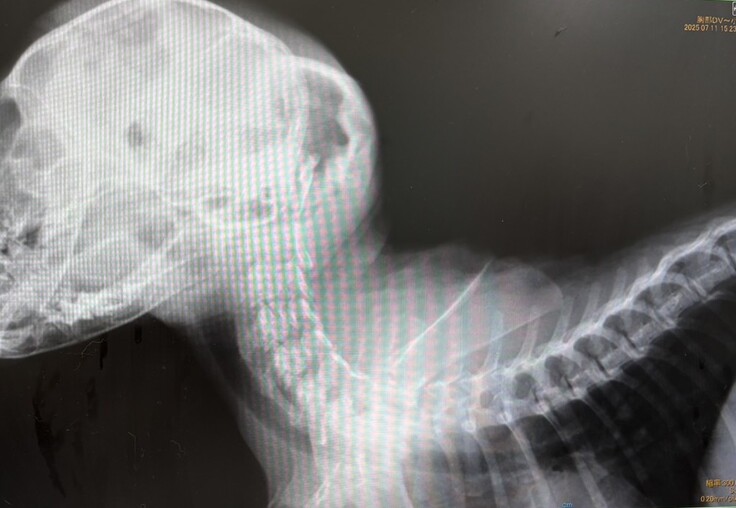

7月10日、ガリガリにやせ細った茶トラの女の子(生後3か月)が倉敷市保健所に収容されました。首は大きく曲がり、手足に力が入りません。後頭部の皮下には大きな血のかたまりがありました。このまま保健所に置いては死を待つばかり・・・。メンバーがかかりつけ医に走り、即日入院となり、点滴と投薬治療が始まりました。